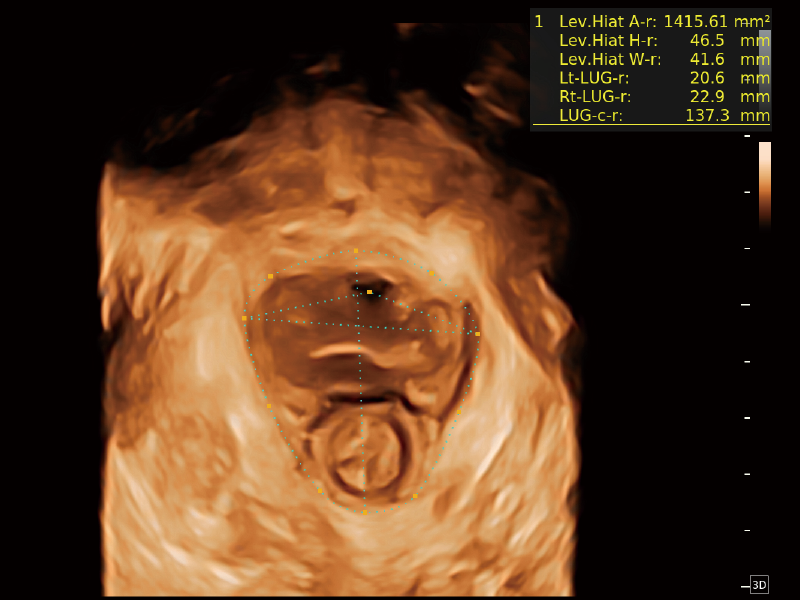

作为开立医疗全新打造的超高端旗舰超声产品,从探头抬起唤醒开启扫查到多维探头发射接收,通过先进的场成像发射、自适应聚合重建等技术,基于RF Data原始射频数据在图像生成、高端功能等方面实现突破,为妇产科、儿科提供全方位临床解决方案。

独有场成像发射技术

自适应聚合重建技术

独家XPUs混合硬件架构